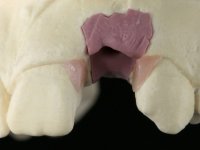

An impression was made on the implant with open tray technique using soft and regular consistency putty. At the laboratory, after confection of the work model, a diagnostic waxing was performed, which sought to find an aesthetic compromise solution. In this sense, a temporary workpiece screwed onto the implant was used to simulate the difficulties we would have with screwing the definitive work. This study abutment consisted of wax to reproduce soft and hard tissues, seeking to anticipate the use of ceramics of gingival and coronary shade. Also, part of the interproximal papillae corresponding to the distal portion of the 2.1 tooth and the mesial tooth of the tooth 2.3 were also waxed, anticipating the use of composite resin “chips” with gingival tonality. Finally, a veneer was waxed to correct the microdontia of the tooth 1.2. In this waxing, the vestibular emergence of the orifice for access to the screw of the implant abutment was evident. Once this therapeutic option was accepted, the implant abutment in polymerized composite resin was prepared at the lab, as well as the papillary "chips", also in composite resin of gingival tonality. Tested in the mouth, the abutment was screwed and the "chips" bonded. The access hole of the screw was filled with composite resin. In subsequent consultation, a gingivectomy was performed on the cervical contour of teeth 1.3, 1.2 and 1.1 with the aim of correcting the asymmetry between the first and second quadrant. After the soft tissues were cicatrized, a dental bleaching was performed according to the patient’s aesthetic requirements. Final impression on the implant was made using the silicone open tray technique, taking care to individualize the transfer piece by copying the emergence profile of the patient’s provisional abutment. At the laboratory, the impression yielded a definitive working model, on which the abutment was waxed on a plastic insert. This process was carried out with the orientation of a wall of silicone based on diagnostic waxing. The wax made on the plastic part was placed in a special holder that allowed its scanning in a laboratory scanner. This scan by CAD process informed the design of an abutment in Zr. later materialized by a CAM process. The Zr. abutment was tested in the mouth, validating its clinical and imaging establishment. During this consultation, the choice of color was made by the ceramist, of both the coronary ceramics and the ceramic of gingival tonality to be used. Individualized color scales were used. At the laboratory, the coronary and gingival ceramics were placed on the implant abutment and later, on a working model with refractory gypsum, a veneer of feldspathic ceramic was made. This veneer was built on a surface specially designed for this purpose in the abutment. This surface tried to reproduce a dental preparation performed for the same effect. In the mouth the abutment was screwed with a torque of 35N, the access hole to the screw was filled with Teflon and later filled with composite resin. The veneer was bonded onto the implant abutment using the conventional bonding technique, with relative insulation. For economic reasons, the patient did not proceed to perform the veneer on tooth 1.2. Although a limited aesthetic compromise was expected from the outset, a result was achieved which satisfied the patient.